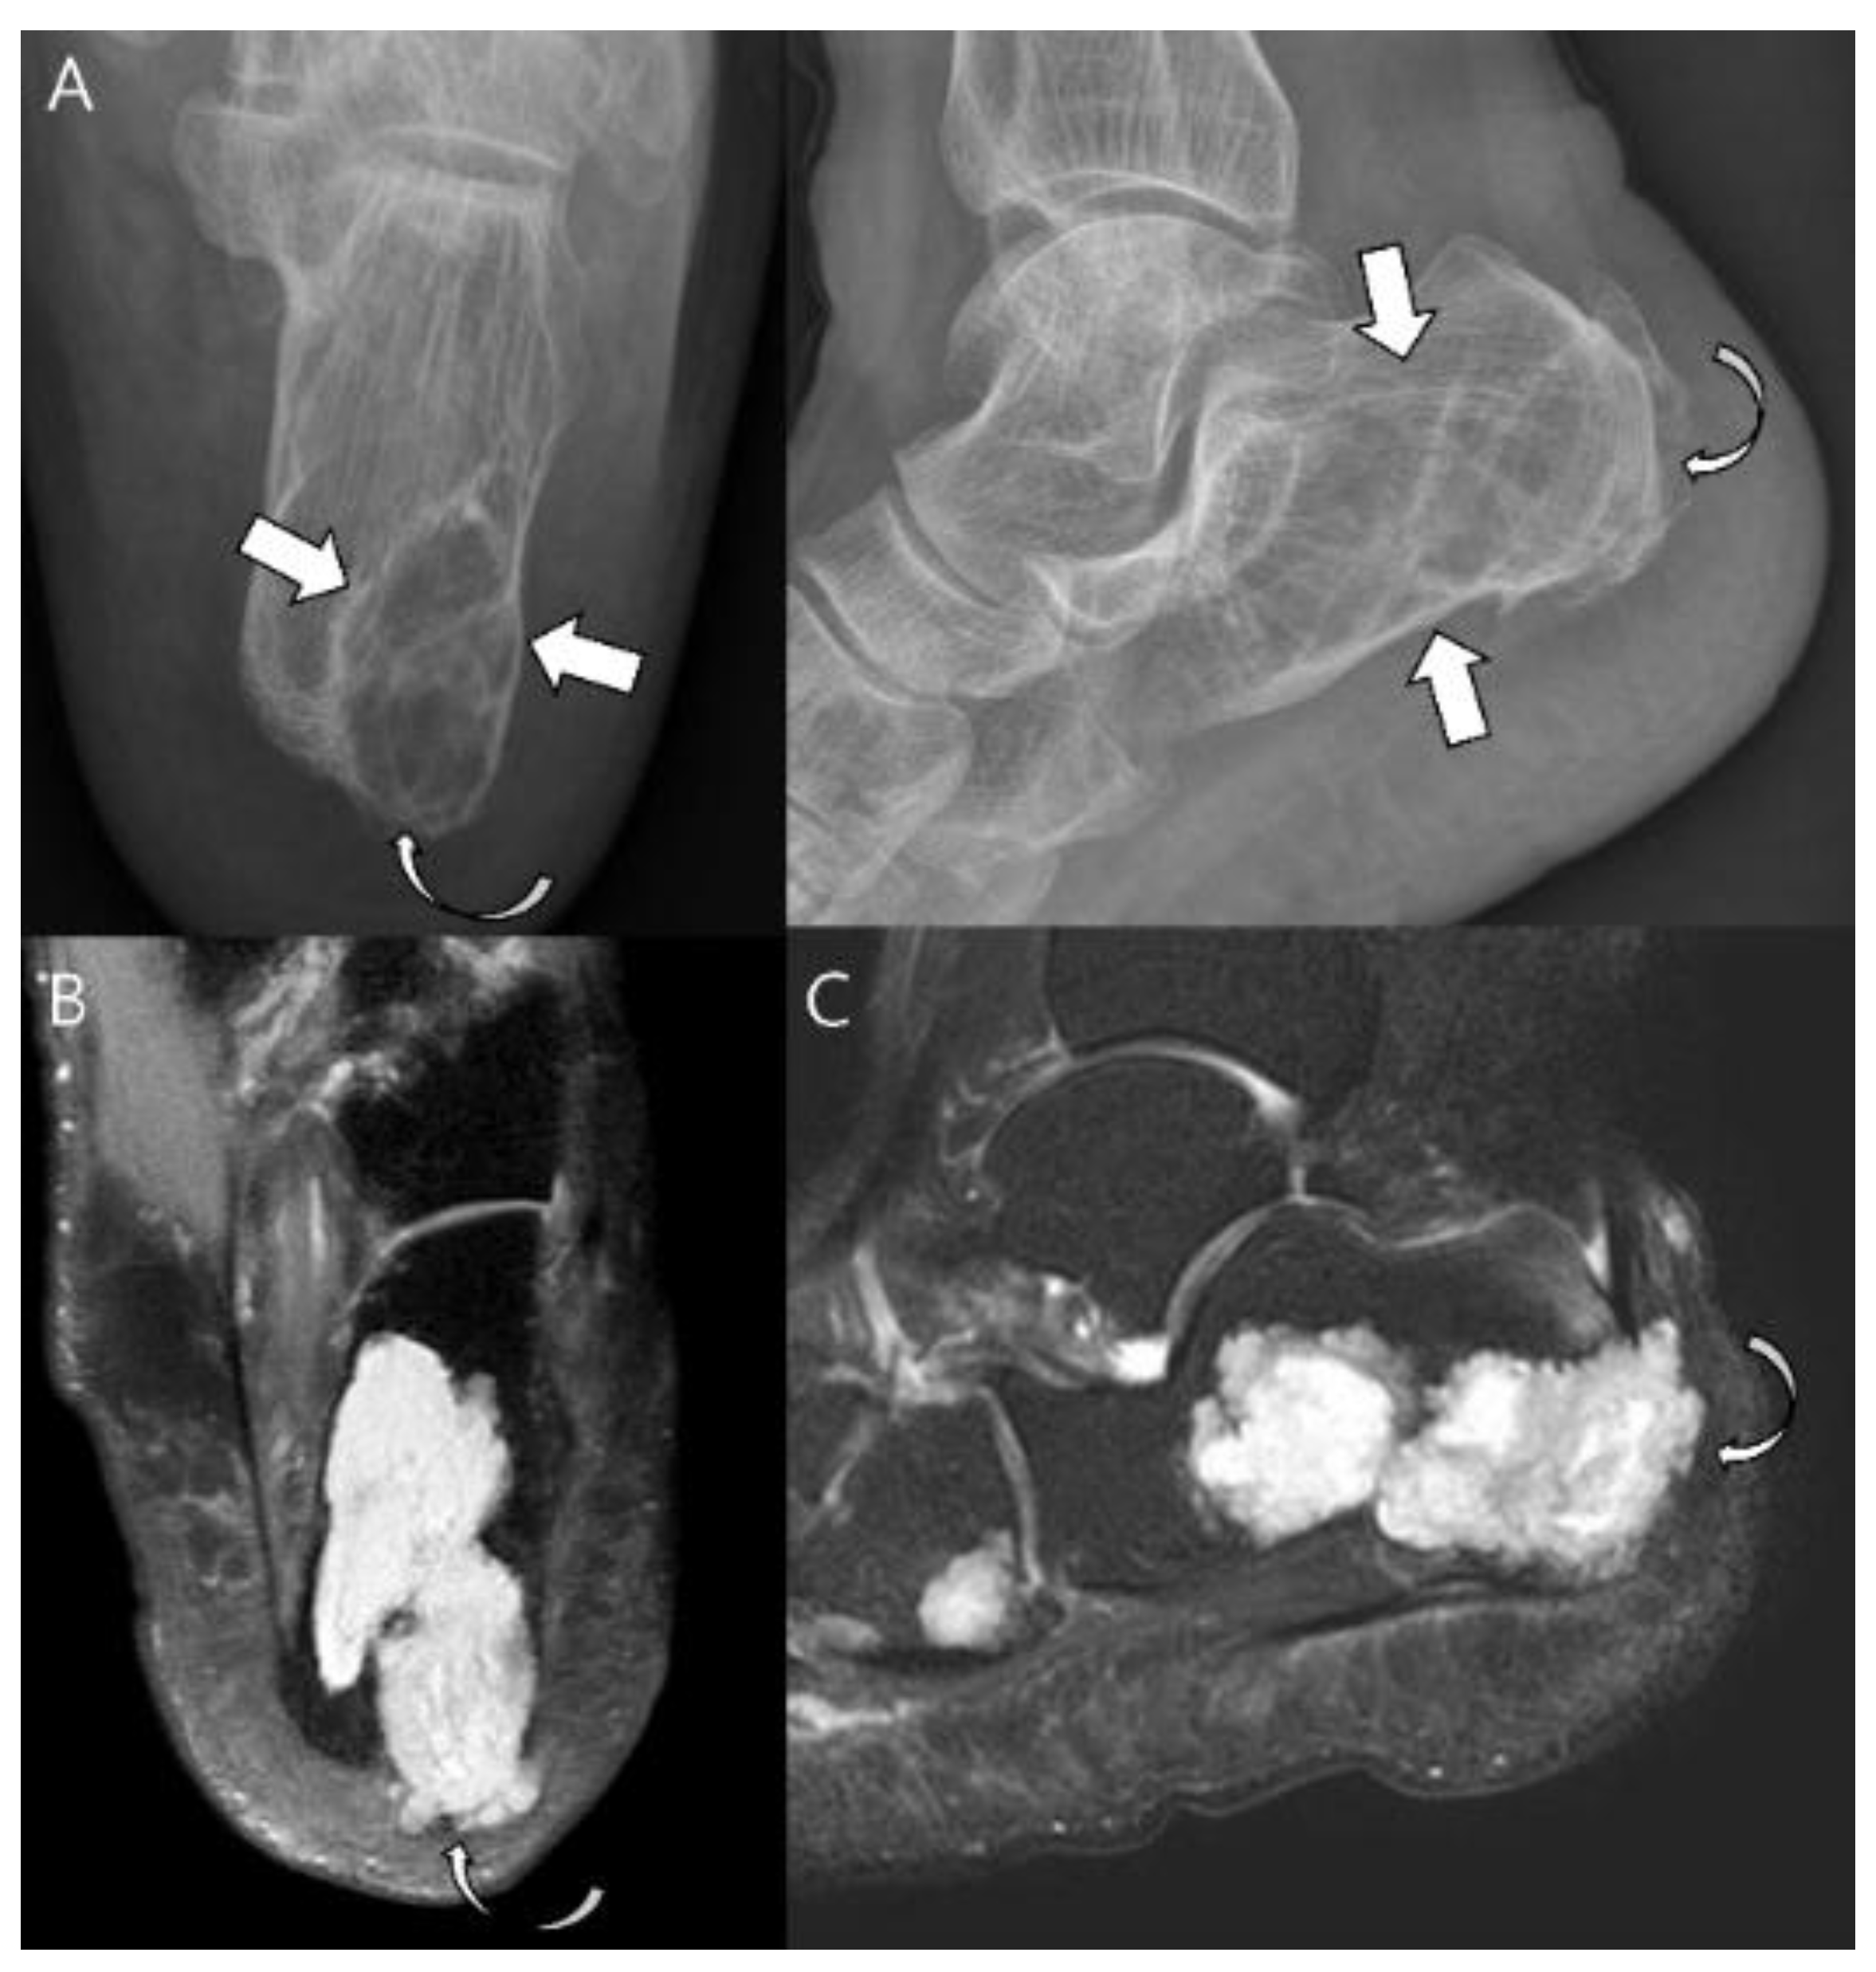

- Robinson, P.; White, L.M.; Sundaram, M.; Kandel, R.; Wunder, J.; McDonald, D.J.; Janney, C.; Bell, R.S. Periosteal chondroid tumors: Radiologic evaluation with pathologic correlation. AJR Am. J. Roentgenol. 2001, 177, 1183–1188. [Google Scholar] [CrossRef]

- Vanel, D.; De Paolis, M.; Monti, C.; Mercuri, M.; Picci, P. Radiological features of 24 periosteal chondrosarcomas. Skelet. Radiol. 2001, 30, 208–212. [Google Scholar] [CrossRef] [PubMed]

- Papagelopoulos, P.J.; Galanis, E.C.; Mavrogenis, A.F.; Savvidou, O.D.; Bond, J.R.; Unni, K.K.; Sim, F.H. Survivorship Analysis in Patients with Periosteal Chondrosarcoma. Clin. Orthop. Relat. Res. 2006, 448, 199–207. [Google Scholar] [CrossRef] [PubMed]

- Bertoni, F.; Boriani, S.; Laus, M.; Campanacci, M. Periosteal chondrosarcoma and periosteal osteosarcoma. Two distinct entities. J. Bone Jt. Surg. 1982, 64, 370–376. [Google Scholar] [CrossRef] [PubMed]

- Nojima, T.M.; Unni, K.K.M.; McLeod, R.A.M.; Pritchard, D.J.M. Periosteal chondroma and periosteal chondrosarcoma. Am. J. Surg. Pathol. 1985, 9, 666–677. [Google Scholar] [CrossRef]